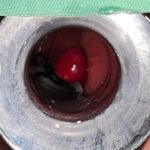

LASER LIAS FOR ANAL FISSURES AND BANDING OF HEMORRHOIDS